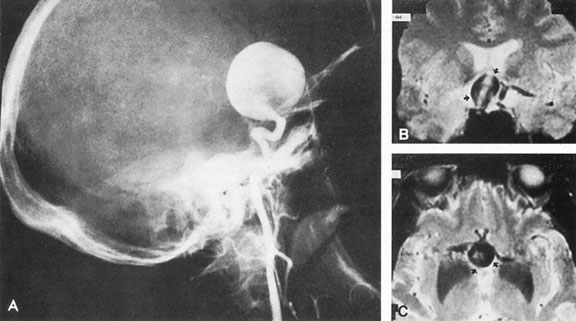

Carotid–Supraclinoid

One of the more insidious and potentially treatable causes of progressive visual loss is unruptured aneurysm of the supraclinoid portion of the internal carotid artery. Here, the term supraclinoid seems more a function of size than of specific site or origin, and distinction between ophthalmic and supraclinoidal types is unclear. Of 3,123 giant (larger than 25 mm) intracranial aneurysms in one series,17 93 involved the internal carotid above the cavernous sinus, thus qualifying as supraclinoid. Sixty-five were carotid–ophthalmic, 16 were at the bifurcation of the middle cerebral artery, and 12 were carotid-posterior communicating-anterior choroidal in location. Bilateral carotid–ophthalmic aneurysms were found in 19 cases, with a female predominance and average age of 48 years. The visual system was compressed in all but 6 cases, and 14 aneurysms presented as subarachnoid bleeding. Most of these giant aneurysms occur in women in the fifth and sixth decades of life, and their effects are primarily the result of compression of the optic nerves and chiasm.17 For the most part, involvement of the visual system represents the only neurologic complication. Such aneurysms may rarely rupture, but most commonly they present as insidious visual loss, or they are uncovered during angiography for other sister aneurysms.18 The pattern of visual field loss with supraclinoid aneurysm and its temporal profile tend to differ from that occurring with primary intrasellar or parasellar tumors. Vision is usually affected in a single eye, commonly with nasal field depression, and at times progressing to blindness before the second eye is involved.19 These aneurysms arise below the optic nerve, which is stretched and flattened before subsequent involvement of the chiasm and the opposite nerve.

Most such aneurysms expand upward and forward, becoming located primarily anteriorly (Fig. 4). The optic nerves rise upward form the optic canal and may be inclined at a 45-degree angle such that the chiasm is more superiorly, as well as posteriorly, placed. It may be expected that uniocular ipsilateral visual loss would occur and progress before the contralateral field is involved because of chiasmal compression and before opposite nerve damage ensues. Although rapid visual loss has been reported, a longer duration (even years) is the rule. Rarely, the aneurysm may be more posteriorly placed or the chiasm more anteriorly fixed, resulting in initial involvement of the optic tract.20

Fig. 4. Giant suprasellar (supraclinoidal) aneurysms. A: Carotid arteriogram (lateral view) shows a huge aneurysm of the internal carotid artery in a 59-year-old woman with progressing visual loss. Coronal (B) and axial (C) magnetic resonance imaging sections of a similar case. Note partial thrombus formation (TR, 2100 ms; TE, 80 ms).